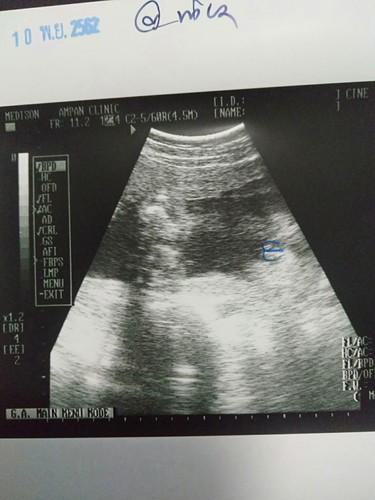

เพศลูก

มีแม่ๆคนไหนมองออกไหมค่ะว่าระหว่างขาอยู่ตรงไหน? หมอกลัวมองไม่ออกเลยวาดมาให้แบบในรูปค่ะ(ดูไม่ออกจริงๆค่ะ) และตอนนี้ตั้งครรภ์ได้30w6dแล้ว ไปซาวด์ดูเพศครั้งแรกหมอบอกเพศหญิง ยังงี้มีโอกาสที่จะเปลี่ยนเป็นชายได้ไหมค่ะ ปล.เราจะซื้อของเตรียมคลอดค่ะ เลยอยากทราบว่าอายุครรภ์เท่านี้แล้วมีโอกาสผิดพลาดไหมค่ะ